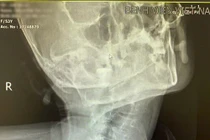

Kết quả chụp X – quang cho thấy anh bị đa chấn thương, gãy nhiều xương như: xương mâm chày, đầu trên xương mác, xương bàn tay, mắt cá trong. Để đưa các mảnh xương gãy về đúng vị trí giải phẫu, ngăn ngừa tổn thương mô lành xung quanh và giúp bệnh nhân sớm phục hồi vận động, các bác sĩ khoa Chỉnh hình vi phẫu đã chỉ định bệnh nhân phẫu thuật cố định xương.

Thế nhưng, khi tìm hiểu kỹ bệnh sử, ê-kíp phát hiện người bệnh bị viêm cột sống dính khớp từ năm 8 tuổi nhưng chưa từng điều trị. Trải qua hơn 20 năm, căn bệnh tiến triển âm thầm, khiến nhiều đoạn cột sống bị dính liền vào nhau, gây cứng khớp, hạn chế vận động cột sống và lồng ngực, bệnh nhân bị gù cột sống cổ và cột sống lưng, không thể nằm ngửa.

Điều này khiến việc gây mê đặt đường thở trở thành thách thức cực kỳ lớn. Bởi để gây mê toàn thân cho bệnh nhân trước khi tiến hành phẫu thuật, bác sĩ thường cần đặt nội khí quản, nhưng với một cột sống biến dạng nặng như vậy, mọi thao tác đều trở nên rủi ro.

Cột sống của bệnh nhân hiện tại không có tính đàn hồi, nếu cố gắng ngửa cổ bệnh nhân để gây mê đặt nội khí quản thì khả năng sẽ làm gãy cột sống bệnh nhân. Chính điều này đã đặt ra một thách thức vô cùng lớn, làm sao để gây mê an toàn cho một cột sống gần như không thể ngửa, ưỡn hay di động?